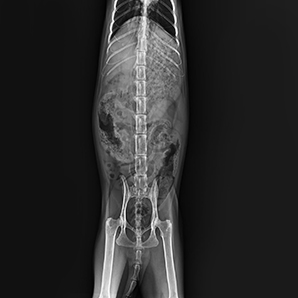

Built on advanced technology in the whole imaging chain, the system delivers a low-dose imaging experience with outstanding image quality for any type of pet. It allows you to finish the exposure with the panel on the tube head, simple operation and instant imaging enable it to use in an easy and fast way for every situation.

Get a high-quality instant image

Instant images on the tube head allow faster diagnoses and enable better communication with animal owners intuitively and clearly.